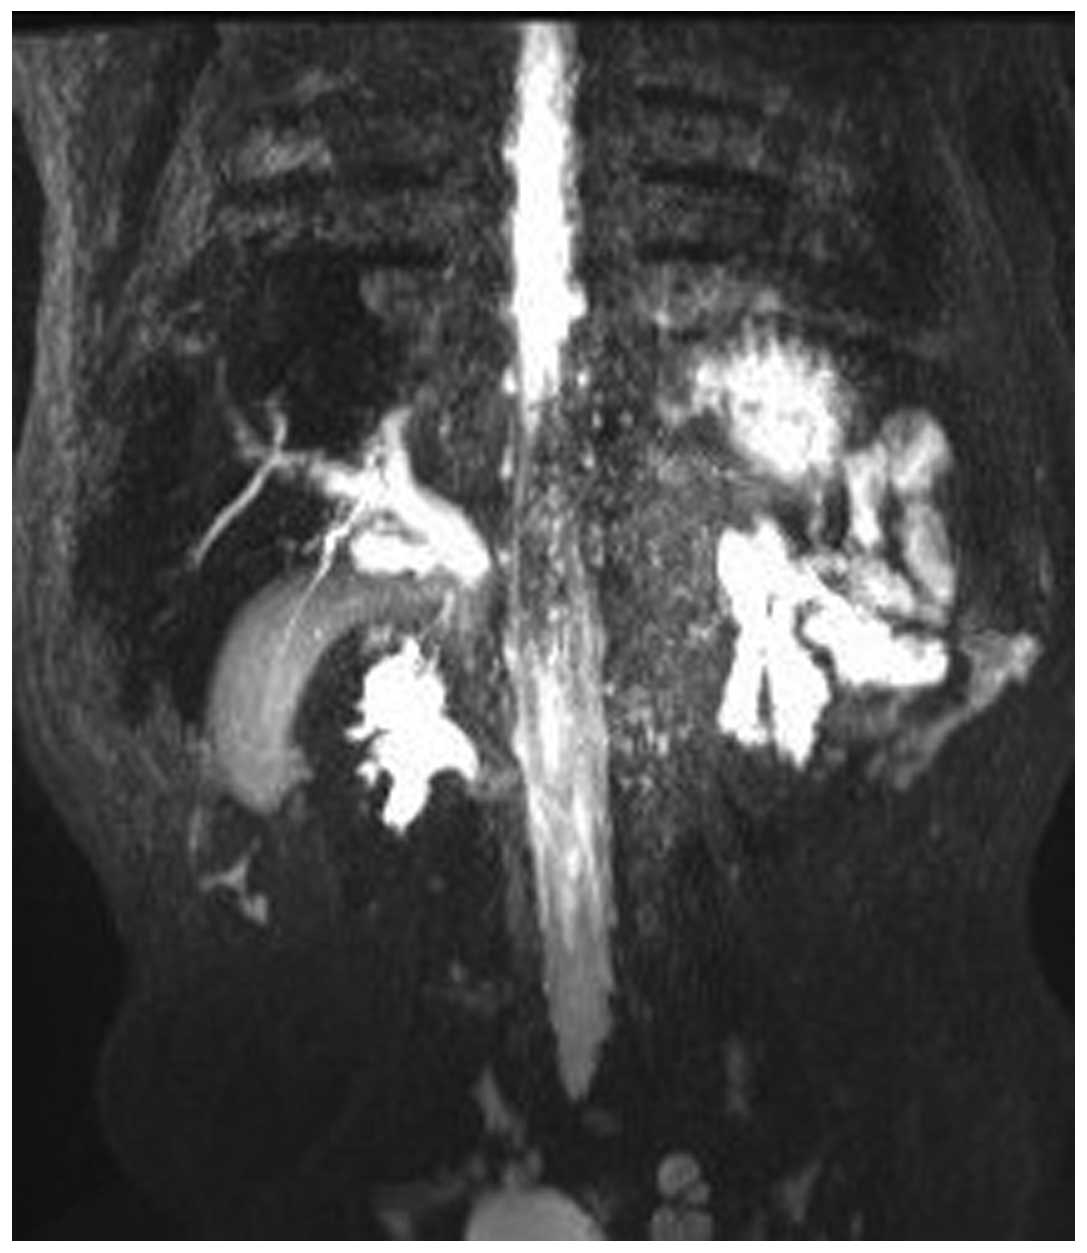

Ultrasonography suggested a pancreatic head body mass, distal common bile duct (CBD) obstruction and proximal CBD dilatation, with a diameter of ~1.5 cm. Magnetic resonance imaging (MRI) showed dilatation in the left and right hepatic ducts, the common hepatic duct and the CBD (Fig. 1), and a pancreatic head and body mass of ~4.7×5.2 cm, with a strong signal. The portal vein and mesenteric vessels were closely linked to the tumor (Fig. 2). Chest computed tomography (CT) did not show any abnormalities.

Figure 2.

Pre-operative magnetic resonance imaging scan showing the tumor in the head of the pancreas encompassing the portal vein and mesenteric vessels, repressing the common bile duct and duodenum.

During the follow-up 3 months after the surgery, the patient showed an increase in body weight, no abdominal pain or jaundice, and urination and defecation were of a normal color. Liver function and pancreatic amylase levels were normal. Ultrasonography showed the size of the pancreatic head mass to be ~4.3×3.6×2.3 cm, which was slightly reduced compared with the pre-operative size. During the follow-up at 28 months post-surgery, the child showed good growth and development, no abdominal pain, a good appetite, and normal urination and defecation. Upon examination, no jaundice was observed in the skin and sclera, and the abdomen was flat and soft. MRI showed the mass to be ~2.4×2.0×1.5 cm, which was a significantly reduced, but it was still closely linked to the mesenteric vessels and portal vein. No pancreatic duct dilatation and slight intrahepatic bile duct dilatation were observed, and there were no abnormal signals in the liver parenchyma (Figs. 5 and 6). Chest radiograph did not show any abnormalities.

Figure 5.

Magnetic resonance imaging scan showing a significantly reduced mass, with linkage to the mesenteric vessels and portal vein at 28 months post-surgery.

Figure 6.

Magnetic resonance imaging showing mild intrahepatic bile duct dilatation and no pancreatic duct dilatation at 28 months post-surgery.